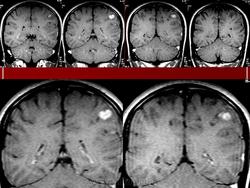

Миксоидная саркома.

1.u.slayd1_.jpg2.u.slayd2_.jpg3.u.slayd3_.jpg4.u.slayd4_.jpg5.u.slayd5_.jpg6.u.slayd6_.jpg7.u.slayd7_.jpg8.u.slayd8_.jpg9.u.slayd9_.jpg10.u.slayd10.jpg